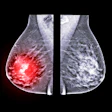

Image-guided biopsy spots residual breast cancer